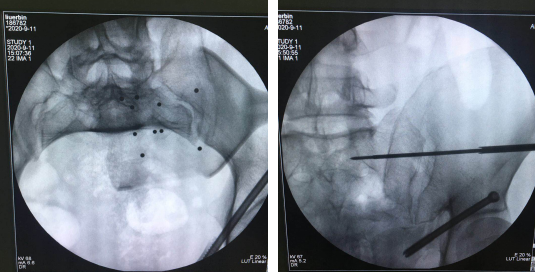

患者51岁,从5米高处坠落,腰臀部疼痛,活动受限,CT显示骨盆多发骨折,任海东主任和手术团队经过讨论,决定给患者进行骨盆骨折机器人导航下复位空心螺钉内固定手术。

术中,任海东主任通过机器人机械臂的精确运动,以及精准定位,规划螺钉方向及长度,避开髋臼缘及盆腔,拧入100mm空心钉固定左侧耻骨上支;再复位骶髂关节,准确地将一枚长度70mm空心螺钉置入,顺利完成骨盆骨折内固定微创手术。此术式对髋臼骨折来说,创伤如此微小——手术切口约1cm、出血量仅50ml,令人惊叹。